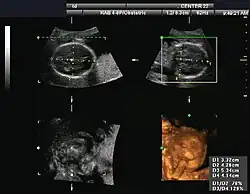

Obstetrical sonography was originally developed in the late 1950s and 1960s by Sir Ian Donald[20][21] and is commonly used during pregnancy to check the development and presentation of the fetus. It can be used to identify many conditions that could be potentially harmful to the mother and/or baby possibly remaining undiagnosed or with delayed diagnosis in the absence of sonography. It is currently believed that the risk of delayed diagnosis is greater than the small risk, if any, associated with undergoing an ultrasound scan. However, its use for non-medical purposes such as fetal "keepsake" videos and photos is discouraged.[22]

Obstetric ultrasound is primarily used to:

- Date the pregnancy (gestational age)

- Confirm fetal viability

- Determine location of fetus, intrauterine vs ectopic

- Check the location of the placenta in relation to the cervix

- Check for the number of fetuses (multiple pregnancy)

- Check for major physical abnormalities.

- Assess fetal growth (for evidence of intrauterine growth restriction (IUGR))

- Check for fetal movement and heartbeat.

- Determine the sex of the baby